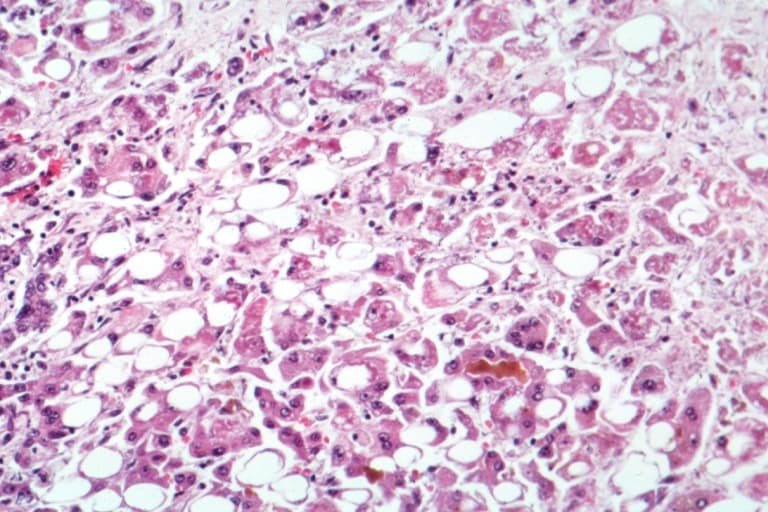

Alcoholic liver disease (ALD), also called alcohol-related liver disease (ARLD), is a term that encompasses the liver manifestations of alcohol overconsumption, including fatty liver, alcoholic hepatitis, and chronic hepatitis with liver fibrosis or cirrhosis. It is the major cause of liver disease in Western countries. Although steatosis (fatty liver disease) will develop in any individual who consumes a large quantity of alcoholic beverages over a long period of time, this process is transient and reversible. More than 90% of all heavy drinkers develop fatty liver whilst about 25% develop the more severe alcoholic hepatitis, and 15% liver cirrhosis. Risk factors known as of 2010 are: Quantity of alcohol taken: Consumption of 60–80 g per day (14 g is considered one standard drink in the US, i.e., 1.5 fl oz hard liquor, 5 fl oz wine, 12 fl oz beer; drinking a six-pack of 5% ABV beer daily would be 84 g and just over the upper limit) for 20 years or more in men, or 20 g/day for women significantly increases the risk of hepatitis and fibrosis by 6% to 41%. Pattern of drinking: Drinking outside of meal times increases up to 3 times the risk of alcoholic liver disease. Sex: Women are twice as susceptible to alcohol-related liver disease, and may develop alcoholic liver disease with shorter durations and doses of chronic consumption. The lesser amount of alcohol dehydrogenase secreted in the gut, higher proportion of body fat in women, and changes in alcohol absorption due to the menstrual cycle may explain this phenomenon. Ethnicity: Higher rates of alcohol-related liver disease, unrelated to differences in amounts of alcohol consumed, are seen in African-American and Hispanic males compared to Caucasian males. Hepatitis C infection: A concomitant hepatitis C infection significantly accelerates the process of liver injury. Genetic factors: Genetic factors predispose both to alcoholism and to alcoholic liver disease. Both monozygotic twins are more likely to be alcoholics and to develop liver cirrhosis than both dizygotic twins.